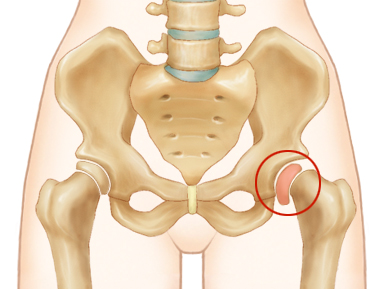

대퇴골두 골단 분리증

[slipped capital femoral epiphysis]

청소년에서 넓적다리 뼈의 윗부분이 특별히 다치지도 않았는데 서서히 어긋나면서 엉덩이 관절이 점차 손상되는 질환

대퇴골두 골단분리증은 성장판이 아직 열려있으나 덩치는 꽤 커진 청소년기에 주로 발생한다. 넓적다리 뼈의 윗부분은 골반뼈와 함께 엉덩이 관절을 이루고 있는데, 골반뼈와 맞닿고 있는 넓적다리 뼈의 윗쪽 끝부분을 대퇴골두라고 한다. 이는 그 아래의 대퇴경부와 성장판으로 연결되어 있는데 대퇴골두 골단분리증은 이 성장판에서 대퇴골두가 특별히 다치지도 않았는데 저절로 서서히 어긋나는 병이다. 사타구니가 아프고 치료를 제대로 하지 않으면 엉덩이 관절이 점차 손상된다. 대부분 대퇴골두가 뒤쪽으로 넘어가게 된다.

고관절의 대퇴골두 부분이 어긋남